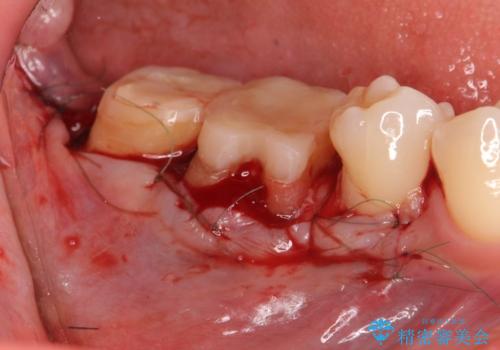

金属のクラウンは薄く加工しても壊れないことがメリットですが、セラミッククラウンを装着するにはスペースが少なすぎ、このまま治療を進めると外れやすく壊れ易いセラミッククラウンの設計となるため、歯周外科を行い狭小なスペースの拡大を行うこととしました。

なんとかギリギリのスペースを確保するこおtができ、無事銀歯を外してセラミック治療を行うことができました。